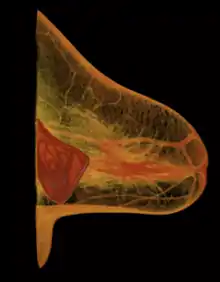

The human body's immune response to a surgically installed foreign object—breast implant, cardiac pacemaker, orthopedic prosthesis—is to encapsulate it with scar tissue capsules of tightly woven collagen fibers, in order to maintain the integrity of the body by isolating the foreign object, and so tolerate its presence. Capsular contracture—which should be distinguished from normal capsular tissue—occurs when the collagen-fiber capsule thickens and compresses the breast implant; it is a painful complication that might distort either the breast implant, or the breast, or both. Capsular contracture is diagnosed through a visual and physical examiniation according to level of increasing severity based on the Baker Grade scale: Baker Grade I, Baker Grade II, Baker Grade III, and Baker Grade IV.

The cause of capsular contracture is unknown, but the common incidence factors include bacterial contamination, device-shell rupture, filler leakage, and hematoma. The surgical implantation procedures that have reduced the incidence of capsular contracture include submuscular emplacement, the use of breast implants with a textured surface (polyurethane-coated);[60][61][62] limited pre-operative handling of the implants, limited contact with the chest skin of the implant pocket before the emplacement of the breast implant, and irrigation of the recipient site with triple-antibiotic solutions.[63][64]

The correction of capsular contracture might require an open capsulotomy (surgical release) of the collagen-fiber capsule, or the removal, and possible replacement, of the breast implant. Furthermore, in treating capsular contracture, the closed capsulotomy (disruption via external manipulation) once was a common maneuver for treating hard capsules, but now is a discouraged technique, because it can rupture the breast implant. Non-surgical treatments for collagen-fiber capsules include massage, external ultrasonic therapy, leukotriene pathway inhibitors such as zafirlukast (Accolate) or montelukast (Singulair), and pulsed electromagnetic field therapy (PEMFT).[65][66][67][68]